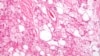

Sebuah rumah sakit pendidikan yang besar di Los Angeles mengatakan bahwa sejumlah pasien diduga telah terpapar dengan bakteri "superbug" yang resisten terhadap obat dlaam prosedur-prosedur endoskopi yang menginfeksi tujuh pasien dan menewaskan dua orang.

Lebih dari 170 pasien yang kemungkinan telah terinfeksi Enterobacteriaceae, atau CRE, diberikan alat penguji di rumah yang akan dianalisis oleh tim dari University of California (UCLA) di sistem rumah sakit Los Angeles hospital system, menurut para pejabat UCLA.

Kemungkinan paparan itu terjadi di Pusat Medis Ronald Reagan di UCLA antara 3 Oktober dan 28 Januari dalam prosedur-prosedur di mana endoskopi dimasukkan ke dalam kerongkongan untuk mendiagnosa dan menyembuhkan penyakit-penyakit pankreatik dan saluran empedu.

Sistem rumah sakit UCLA mengatakan CRE itu kemungkinan ditularkan pada pasien dari dua dari tujuh alat yang digunakan di pusat tersebut, semuanya diproduksi oleh by Olympus Medical Systems Group.

Pihak rumah sakit mengatakan 179 orang kemungkinan terpapar, tujuh diantaranya telah dikukuhkan mengalami infeksi dan dua diantaranya telah meninggal dunia.